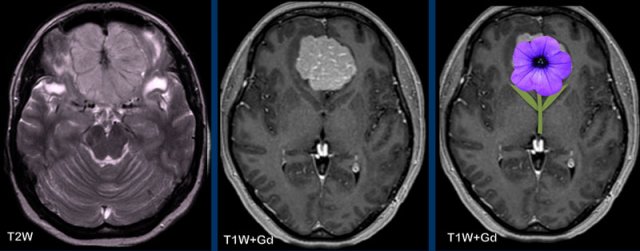

The sunburst sign can give the appearance of a flower like in this anterior skull base meningioma’s

These

images are of a 56-year old woman with breast cancer.

She had a skull lesion at a bone scan nine years earlier

which was thought to be a metastasis.

Now she presented with vomiting and headache.

Images

There is a a large extra-axial lesion compatible with a meningioma.

There is profound hyperostosis of the skull and invasion of the superior sagittal sinus.

This is not a bone metastasis because of these findings and the fact that the lesion is present for nine years.